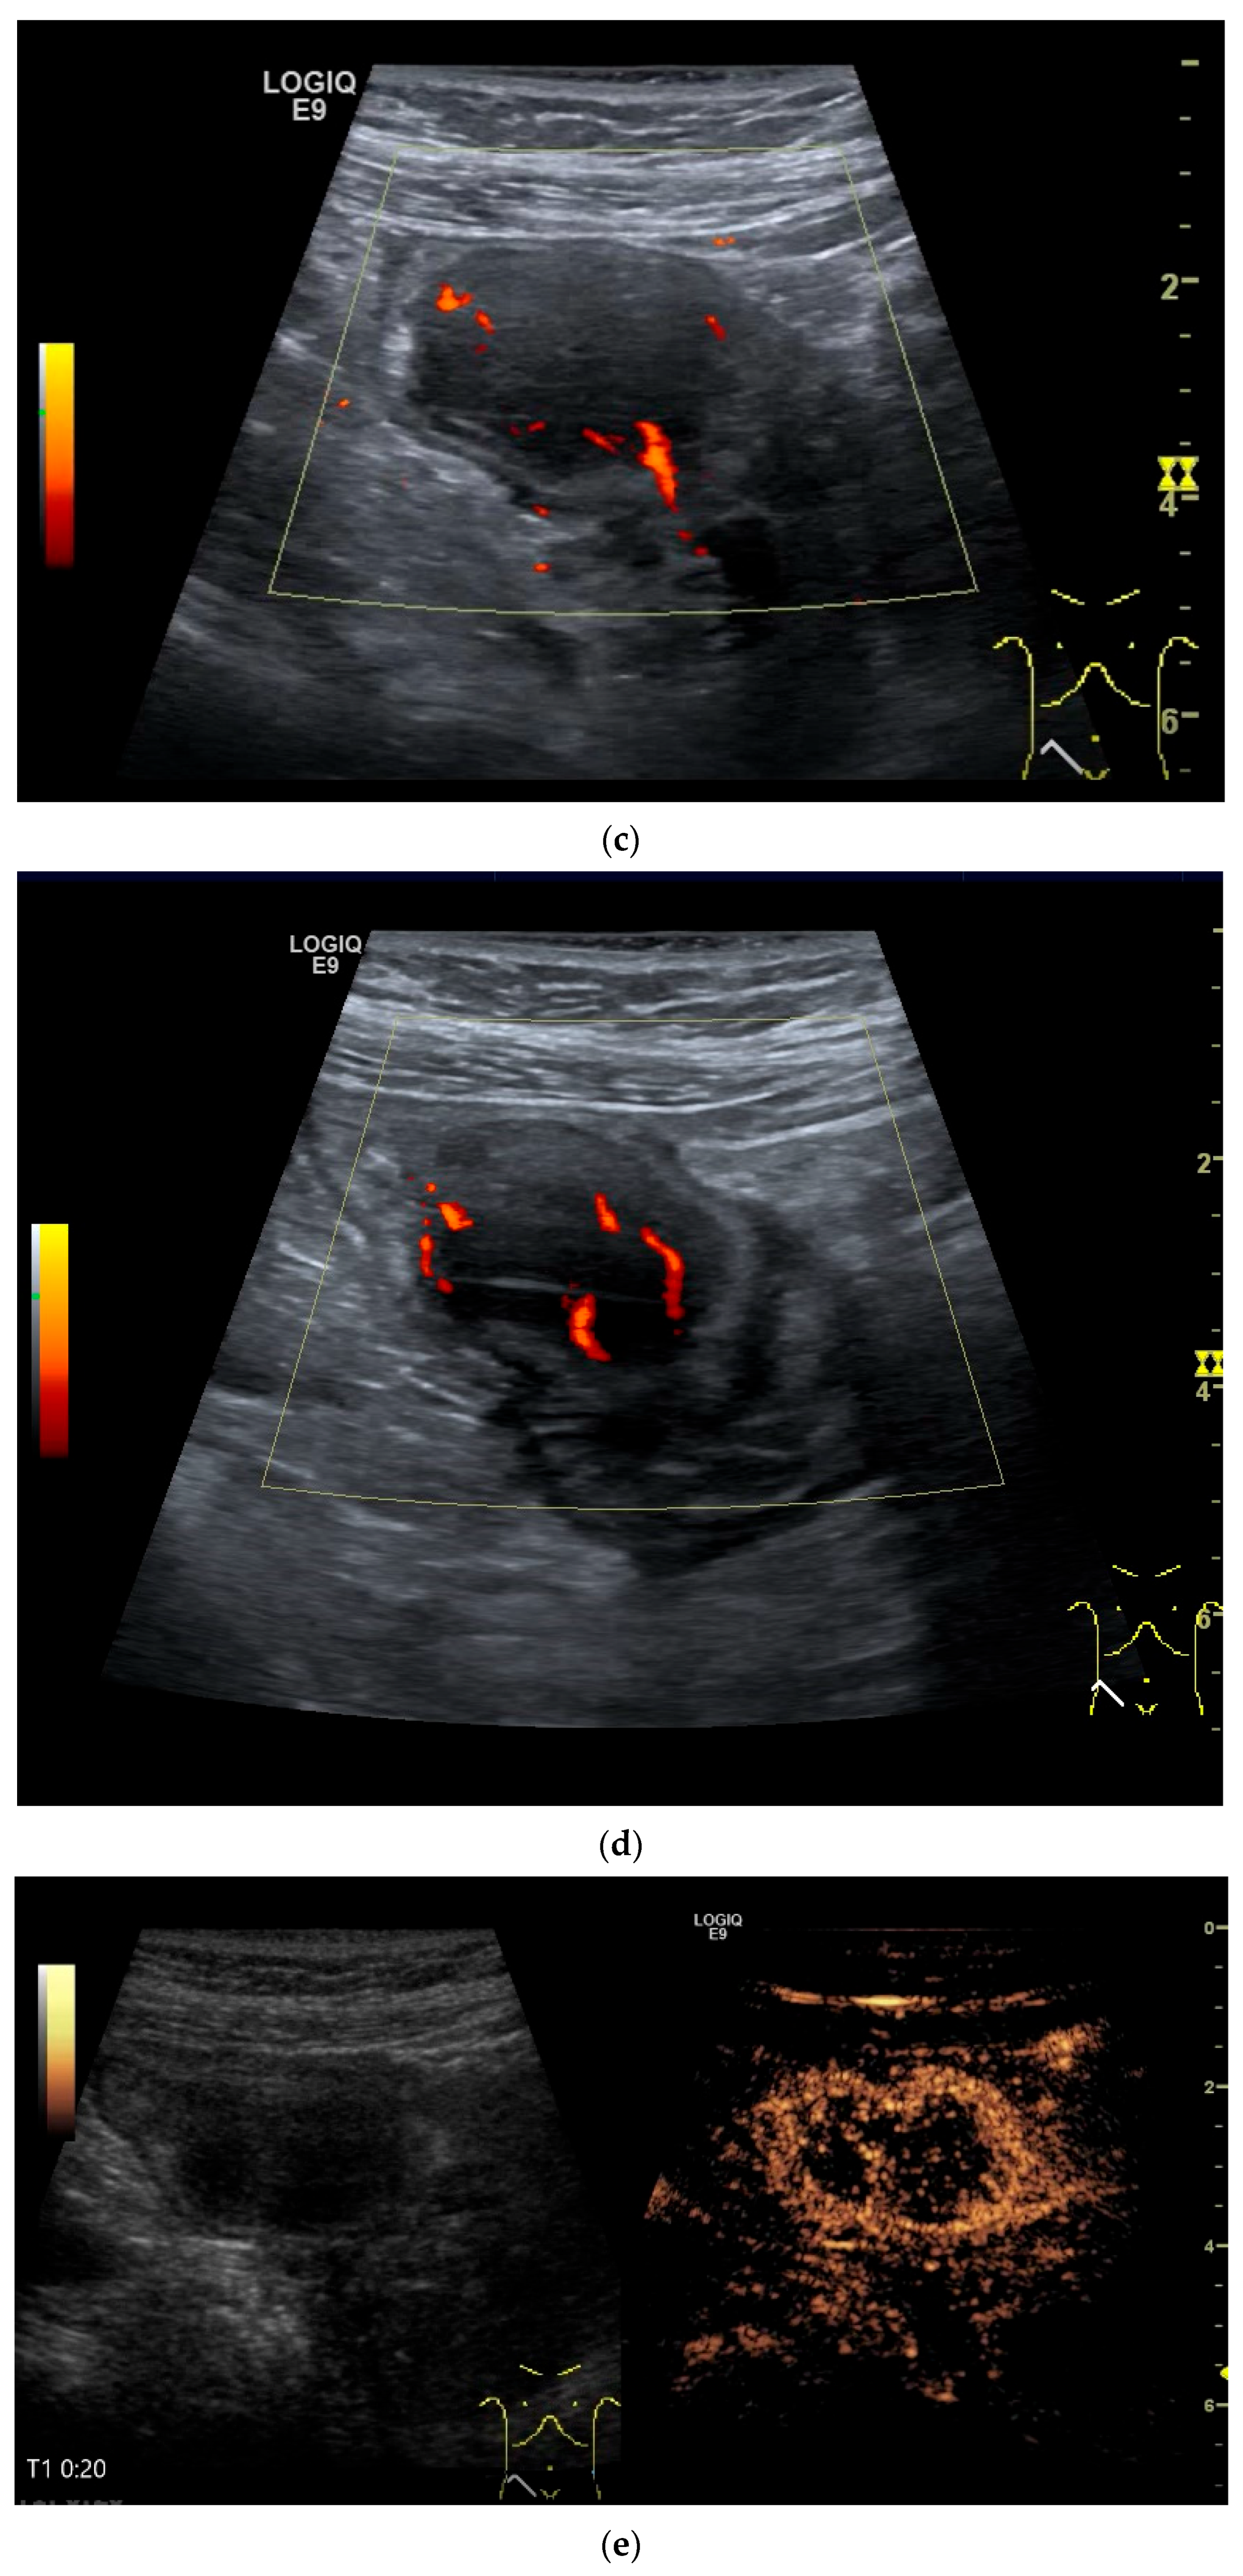

- Cui, N.Y.; Gong, X.T.; Tian, Y.T.; Wang, Y.; Zhang, R.; Liu, M.J.; Han, J.; Wang, B.; Yang, D. Contrast-enhanced ultrasound imaging for intestinal lymphoma. World J. Gastroenterol. 2021, 27, 5438–5447. [Google Scholar] [CrossRef]

| Lymphoma | Very pronounced wall thickening with marked hypoechogenicity. Large regional and distant lymph nodes. Look for splenic infiltration. Tumor vessels on CDI and hyperenhancement on CEUS. Heterogeneous hyperechogenicity of the mesentery with walling of the mesenteric vessels. Multiple localizations are possible. |

| GIST | Round hypoechoic masses, homogeneous or heterogeneous depending on size. They usually originate from the muscularis propria, which can be difficult to distinguish in US. Small vessels on CDI, hyperenhancement on CEUS. They move with the small intestine and can change position. |